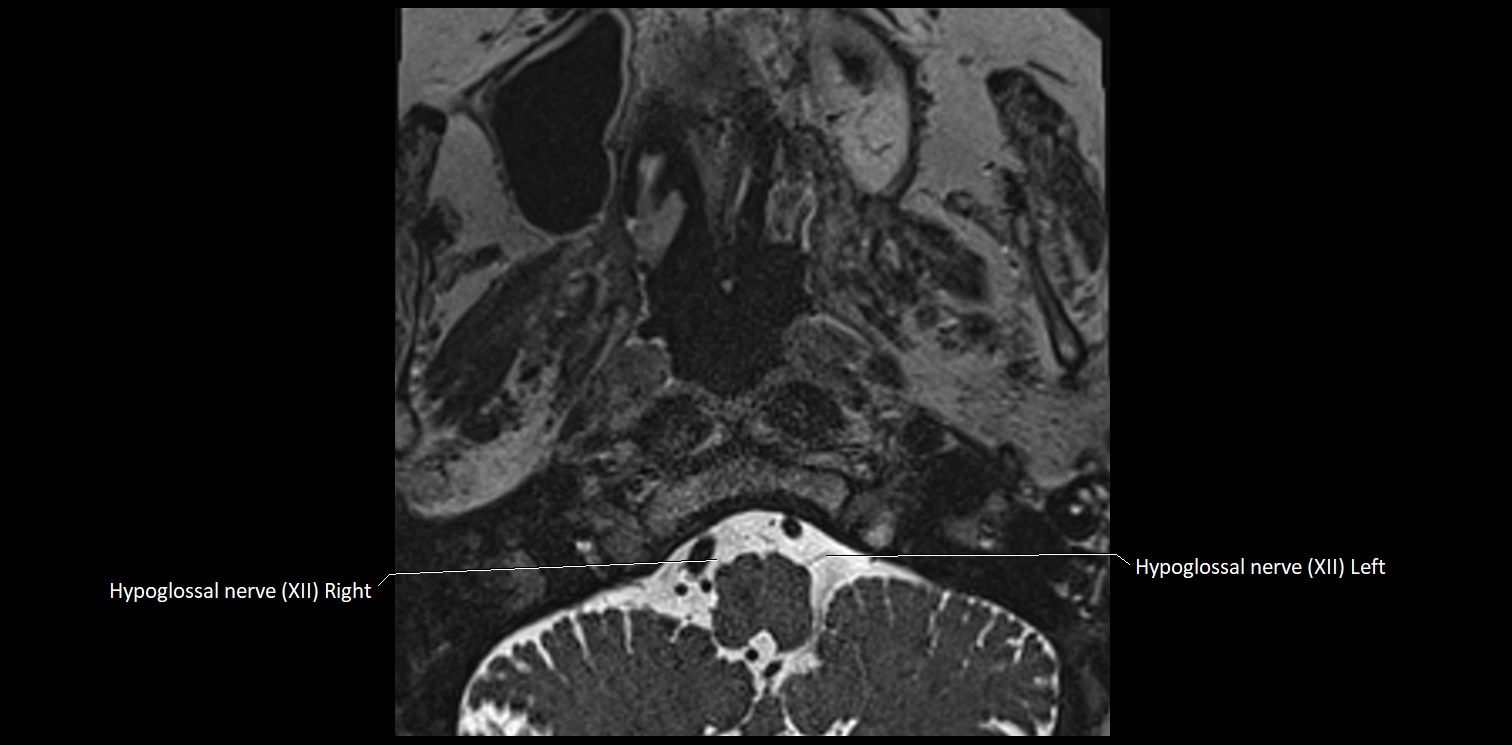

MRI images

image